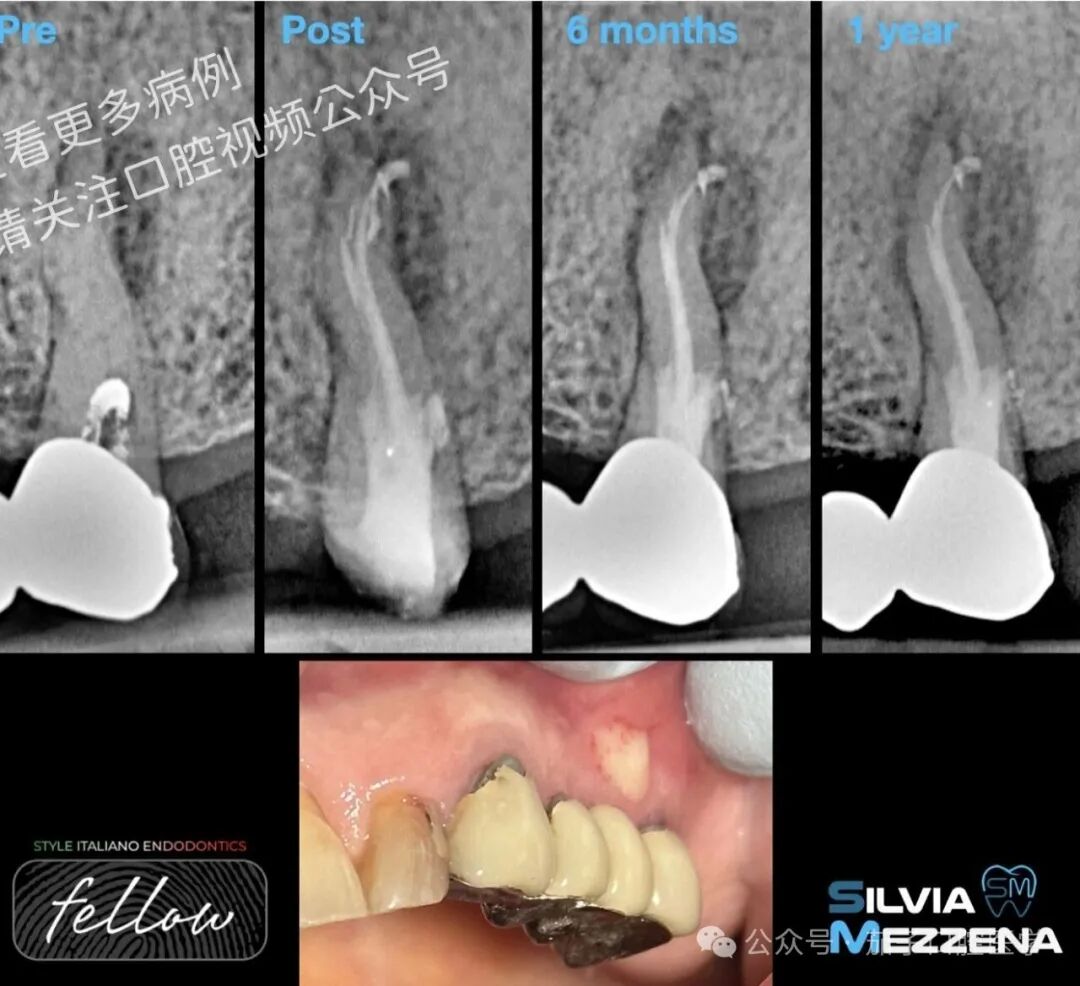

图1一名82岁女性患者因咀嚼时2.5号牙疼痛前来就诊。临床检查显示该牙叩诊阳性,无病理性牙周探诊深度,但存在窦道。术前根尖片显示根管治疗不完善、存在根尖周炎(AP)以及根部远中区域可能存在穿孔。基于临床与影像学表现,诊断为既往治疗牙伴慢性根尖脓肿。鉴于患者已服用双膦酸盐2年,决定首选牙髓再治疗;此外,患者要求保留现有固定桥修复体。

图2二次根管治疗。实施单次就诊再治疗。固定桥顺利拆除,开髓后使用#1 Munce车针机械清除髓腔内未知封闭剂。发现髓室远中壁穿孔,但决定先完成根管预备再处理穿孔。此阶段选用Gold Rotary系统,根管成形至ISO 20.07锥度(F1)。冲洗采用5%次氯酸钠、17% EDTA配合超声激活。充填选用氧化锌丁香油基根管封闭剂及Thermafil充填系统。术后X线片显示根尖区存在多支分叉,舌侧根充填欠佳,可能因解剖性阻塞(Thermafil?K锉?)。鉴于取出根尖潜在分离器械将进一步削弱牙体结构,决定采取严密随访策略。

图4术后6个月内牙齿无症状,窦道消退。不幸的是,9个月后窦道再次出现脓液引流,遂中断双膦酸盐治疗。一年后影像学随访显示根尖周炎加重,遂计划行牙髓显微外科手术。开具药物治疗方案如下:阿莫西林/克拉维酸钾1 g + 甲硝唑250 mg(术前3天起每12小时各服1片,术后继续7天)。

图8术后6个月,患牙无症状且功能正常,根尖周炎已见初步愈合,患者获准重新开始双膦酸盐治疗。窦道及脓液引流已消失。下图展示术后一年半的组织状态。